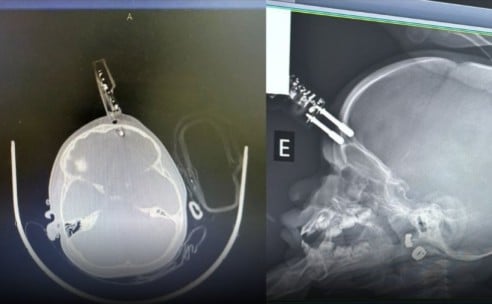

Uma menina de 1 ano passou por cirurgia de urgência, na terça-feira (13), após cair da cama e ter um carregador cravado na testa. O caso aconteceu em Divinópolis (MG).